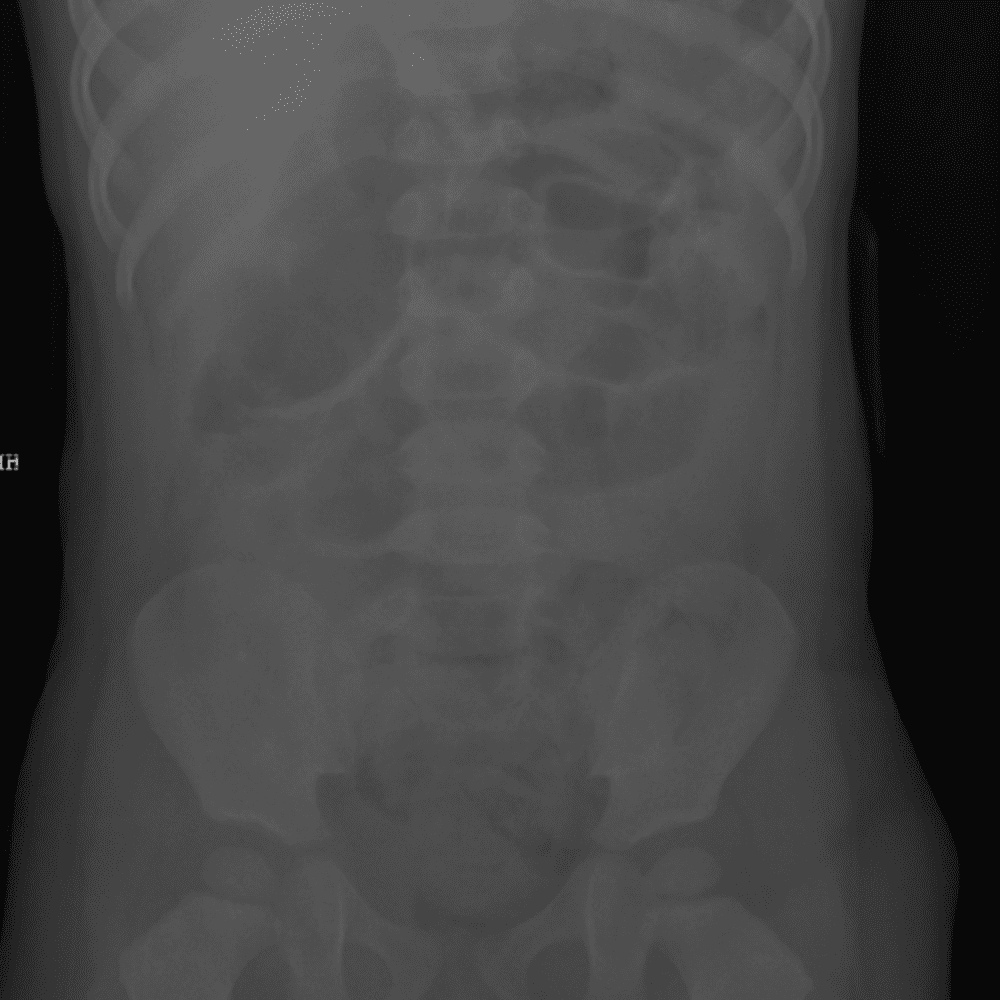

Peds Abdomen

Practice

Simulates call by including subtle or difficult cases and some normals.

30 cases